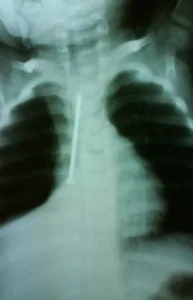

“الطفلة كانت تضحك وتتنفس طبيعي، لم تظهر عليها أي علامة غير طبيعية، لكن إصرار الأم على أنها بحثت جيدًا جعلني أطلب أشعة سينية… وهنا كانت المفاجأة المذهلة: مسمار بطول القفص الصدري تقريبًا داخل جسدها!